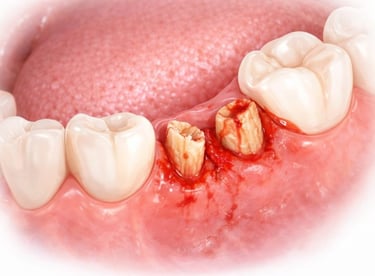

All images shown here represent real clinical cases of teeth extractions done at our dental clinic with patient consent.

Illustrative images and similar real clinical cases requiring tooth extraction